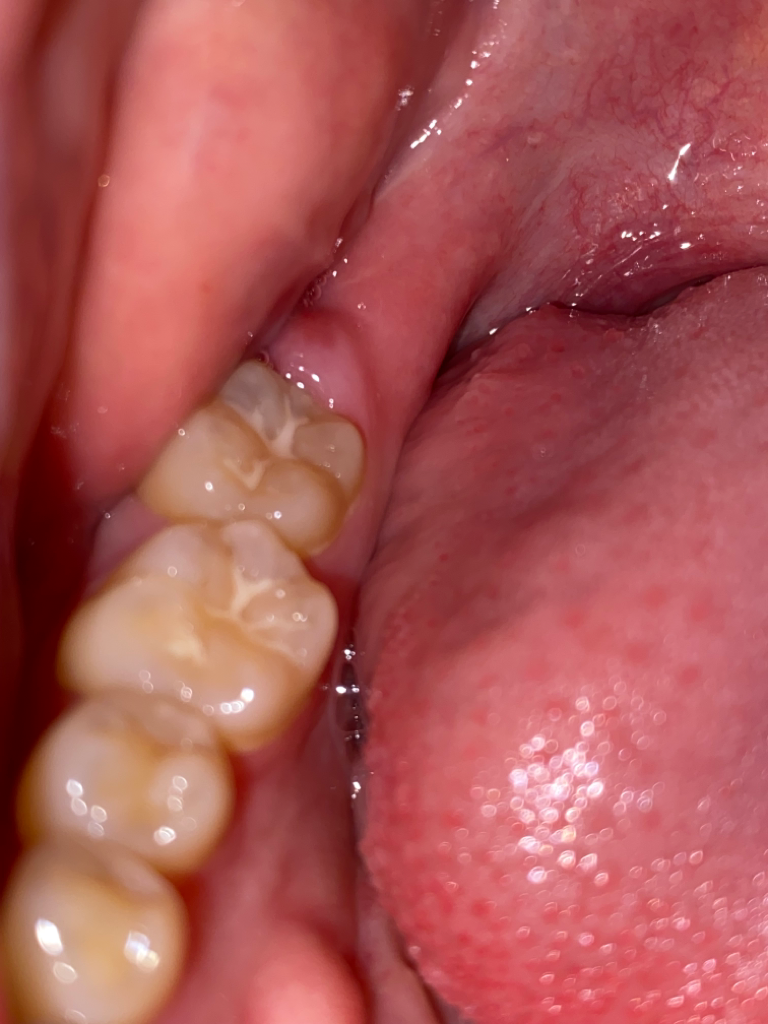

하악 사랑니 발치 후 잇몸이 이상하게 차오르면서 피가 납니다

사진 첨부했습니다

근데 지금 보니 발치한 부위가 볼록 튀어나와있고 튀어나온 살 안쪽으로는 아직 살이 다 차오르지 않았는지 피가 납니다

• 1번 째 사진

• 2번 째 사진